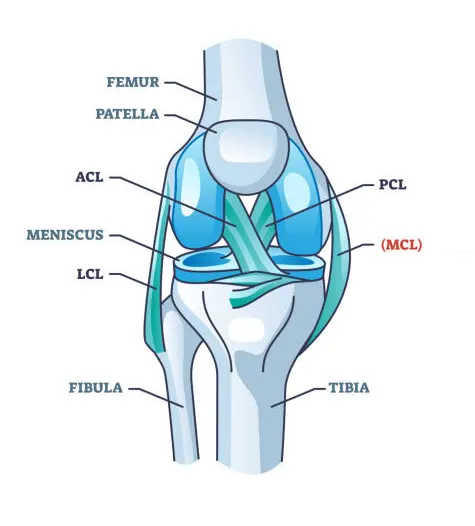

ACL/PCL/MCL Reconstruction

ACL, PCL, and MCL are crucial ligaments within the knee joint, ensuring stability and preventing abnormal movements. When these ligaments suffer severe tears, reconstruction surgery becomes necessary. Typically, this type of surgery is required following high-energy injuries like car accidents or falls from significant heights.

Here are some of the common causes of ligament tears that may require reconstruction surgery:

- Anterior cruciate ligament (ACL) injury: This is the most common knee ligament injury, often caused by pivoting motions with a planted foot.

- Posterior cruciate ligament (PCL) injury: This is less common than an ACL injury and is usually caused by a forceful blow to the front of the knee, such as a car accident.

- Medial collateral ligament (MCL) injury: This injury is often caused by a blow to the outside of the knee.

The decision of whether or not to have ACL/PCL/MCL reconstruction surgery will depend on the severity of the tear, your activity level, and your overall health.

Menisectomy Surgeries

A meniscectomy is a surgical operation that involves the removal of either the entire or a portion of a torn meniscus. The meniscus is a C-shaped cartilage that functions as a shock absorber and stabilizer within the knee joint. Each knee contains two menisci: the medial meniscus located on the inner side of the knee and the lateral meniscus situated on the outer side.